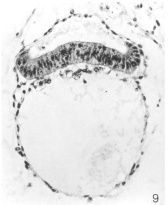

Carnegie Stage 6 Figures

Amniotic cavity, embryonic disc, umbilical vesicle

Embryonic disc

Amniotic cavity